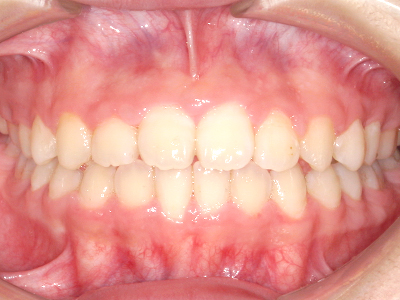

【4】矯正治療

矯正装置を装着し、調整しながら少しずつ歯を移動させ、歯並びを整えていきます。

状態によって家庭でのトレーニングが必要な場合もあり、治療期間も個人差があります。

あくまでも平均値ではありますが、一般的には月1回程度来院頂き、1~2年程度を目安に治療を進めていきます。